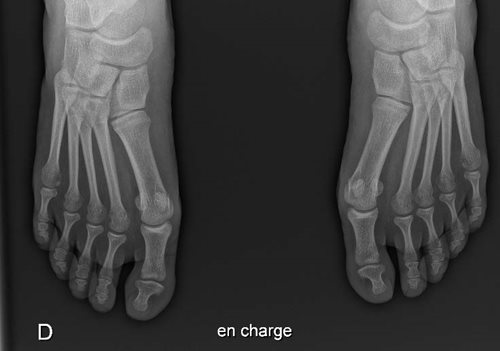

Les subtilités de la technique chirurgicale varient selon les chirurgiens. Néanmoins, tous réalisent une libération latérale des tissus mous et une coupe osseuse (ostéotomie du métatarsien type scarf dans notre institution). Une ostéotomie de la première phalange (type Akin) est parfois nécessaire selon la déformation de celle-ci. Ces gestes permettent de restaurer un valgus physiologique de l’articulation métatarso-phalangienne et de rechausser les sésamoïdes sous le premier métatarsien (figure ci-dessous). Notons qu’en cas d’irréductibilité de la déformation (testée en consultation) ou d’arthrose importante (vue sur le bilan RX), une arthrodèse (fusion) de l’articulation, en position réduite, sera réalisée.

Radiographie à 15 jours puis en charge à 3 mois post-opératoire (scarf autostable bilatéral + Akin P1 droite)